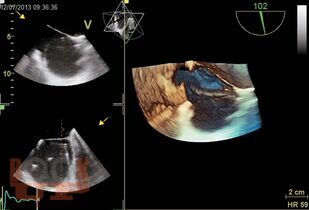

Книга посвящена методу чреспищеводной эхокардиографии, в основном многоплановой чреспищеводной эхокардиографии, которая в настоящее время является наиболее распространенным вариантом чреспищеводного исследования. Уделено внимание вопросам безопасного использования этого высокоинформативного метода. Подробно анализируются возможные осложнения и меры предосторожности при выполнении исследования. Приведены основные доступы и позиции при многоплановой чреспищеводной эхокардиографии и способы их выведения, терминология доступов и позиций, а также манипуляций датчиком. Основные ультразвуковые позиции сопоставлены с топографическими сечениями на анатомической модели чреспищеводного симулятора. Описаны сердечные структуры в норме и при различных патологических состояниях. Представлены возможности и ограничения метода, его клиническое значение.